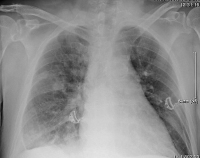

Thoraxröntgen

Abbildung 2: Thoraxröntgen am Aufnahmetag

Kardiologie

pathologischer Befund